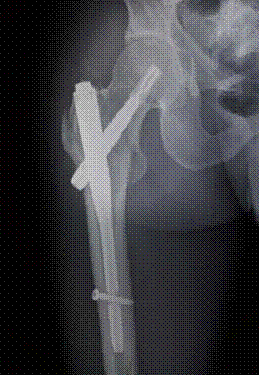

2.患者,男,35岁,入院诊断“右股骨粗隆间粉碎骨折”。

图5:术前X线片 图6:术后X线片